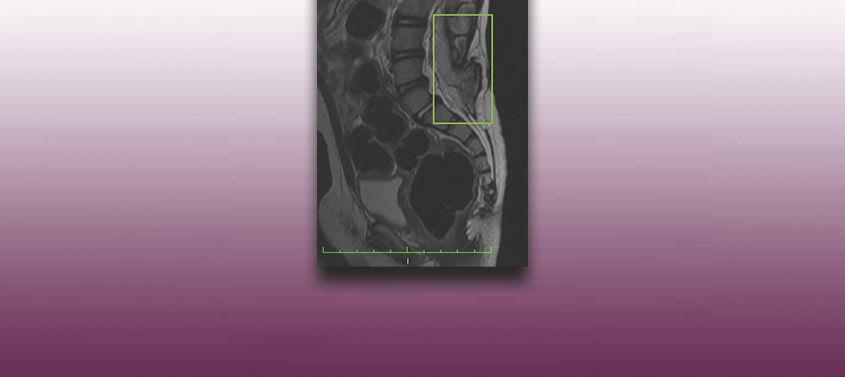

Médula anclada con espina bífida oculta

Última actualización: 20/03/2026, Dr. Miguel B. Royo Salvador, Numero colegiado 10389. Neurocirujano y Neurólogo. Definición En condiciones normales, la médula espinal se encuentra sujeta dentro del canal vertebral únicamente por los ligamentos dentados y el filum terminale, un ligamento que une el cono medular con las primeras vértebras del coxis. Cuando, en cambio, la movilidad […]